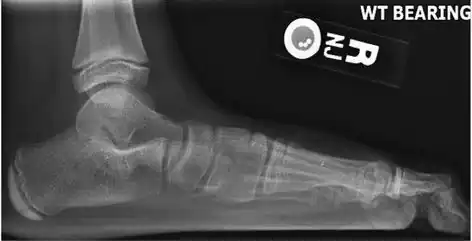

On plain radiography, flat feet can be diagnosed and graded by several measures, the most important in adults being the talonavicular coverage angle, the calcaneal pitch, and the talar-1st metatarsal angle (Meary's angle).[11] The talonavicular coverage angle is abnormally laterally rotated in flat feet.[11] It is normally up to 7 degrees laterally rotated, so a greater rotation indicates flat feet.[11] Radiographies generally need to be taken on weightbearing feet in order to detect misalignment.[12]

Weight-bearing lateral X-ray showing the measurement of calcaneal pitch, which is an angle of the calcaneus and the inferior aspect of the foot, with different sources giving different reference points.[13] A calcaneal pitch of less than 17° or 18° indicates flat feet.[11] -

Same lateral X-ray showing the measurement of Meary's angle, which is the angle between the long axis of the talus and first metatarsal bone.[11] An angle greater than 4° convex downward is considered a flat foot, 15° - 30° moderate flat foot, and greater than 30° severe flat foot.[11]